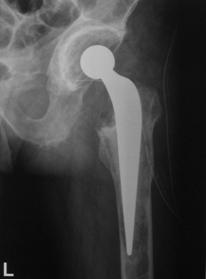

Decimentarea aseptica a componentei femurale

Desi artroplastia totala de sold este o interventie chirurgicala bine standardizata si rezultatele obtinute in privinta ameliorarii simptomatologiei si prevenirea pozitiilor vicioase, uneori se produce decimentarea componentei femurale, fara a avea drept cauza infectia.